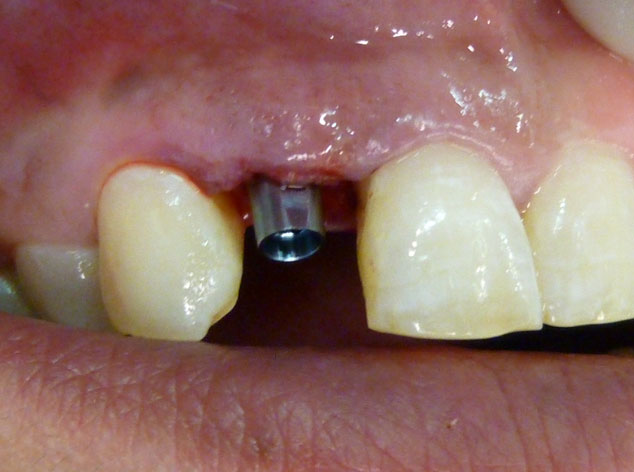

En estos casos han sido tratados con la filosofía de all-at-once, en la

misma sesión: